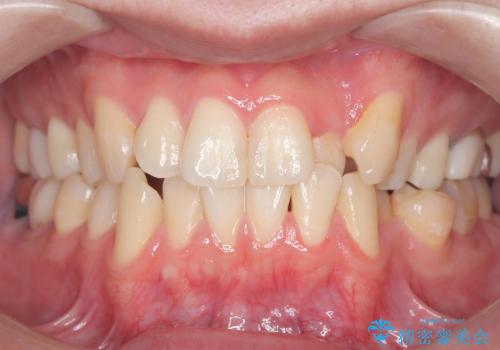

歯科衛生士による、歯石や着色除去の前後写真です。

- 毎日の喫煙による着色を気にして来院されました。前歯から奥歯まで広い範囲で着色が認められたため、歯科衛生士による専門的な機械を使用したPMTC(自費クリーニング)を行いました。